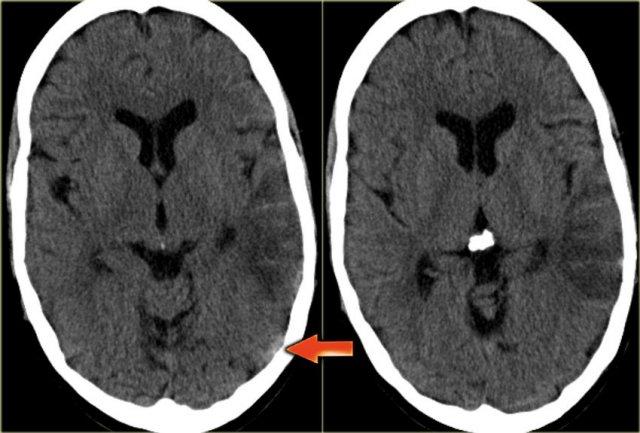

Dấu hiệu cục máu đông tăng tỷ trọng (2)

Hình ảnh tĩnh mạch vỏ não bị huyết khối biểu hiện dưới dạng một dải hoặc đường tăng tỷ trọng hình dây thừng còn được gọi là dấu hiệu dây thừng (cord sign).

Một thuật ngữ khác thường được sử dụng là dấu hiệu mạch máu tăng tỷ trọng (dense vessel sign).

Dấu hiệu cục máu đông tăng tỷ trọng (3)

Hình ảnh bên trái là của một bệnh nhân có nhồi máu xuất huyết ở thùy thái dương (mũi tên đỏ).

Lưu ý xoang ngang tăng tỷ trọng do huyết khối (mũi tên xanh dương).